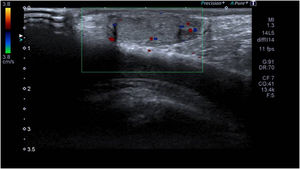

La ecografía escrotal preoperatoria mostró un teste derecho ligeramente aumentado de tamaño, con ecogenicidad heterogénea del parénquima, pérdida del contorno y de la continuidad de la túnica albugínea (flecha azul), ausencia de flujo intratesticular y hematocele (estrella). Las flechas blancas señalan la línea de fractura testicular.

Niño de 10años que acudió a urgencias por dolor testicular derecho de 2horas de evolución tras recibir un traumatismo directo jugando al fútbol. La exploración física revelaba aumento de volumen hemiescrotal derecho, teste derecho muy doloroso a la palpación, con contorno irregular y transiluminación negativa. La ecografía escrotal era sugestiva de rotura testicular derecha (fig. 1). Se indicó cirugía urgente. Se evidenció rotura completa de teste derecho y cuerpo del epidídimo. Se realizó la reparación con material reabsorbible (fig. 2). La evolución postoperatoria fue favorable y se fue de alta a las 24horas. Tras un año de seguimiento, se constata una adecuada viabilidad del teste derecho (fig. 3).